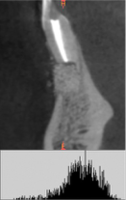

Деминерализованная спонгиоза «Лиопласт»® является рентгенонегативной. Плотность материала, измеренная в первый день после операции РВК (209,08±25,1) оказалась намного меньше плотности здоровой костной ткани (391,25±28,83).

Это объясняется полной декальцинацией этого материала в процессе изготовления и отсутствием в нем минеральных компонентов (рис. 1).

Рис. 1. Гистограмма распределения плотности на дентальной компьютерной томографии фронтального отдела верхней челюсти пациентки О. непосредственно после операции РВК зуба 1.1, 1.2 с заполнением костной полости деминерализованной спонгиозой «Лиопласт»®.

При использовании деминерализованной спонгиозы «Лиопласт»® через 3 месяца уровень поглощения (HU) костной ткани, формирующейся в области дефекта приближается по своему к плотности реперной зоны.

Средний прирост плотности костной ткани у пациентов I группы составил 86% (табл. 1).

Образование новой костной ткани доказывает соотношение плотности операционной области к здоровой костной ткани, которое в первый день после РВК составляло 0,53±0,04. , а к концу третьего месяца его значение увеличилось практически в 2 раза и приблизилось к единице (рис.3).

Основываясь на данных клинико-рентгенологического исследования был поставлен диагноз «хронический апикальный периодонтит 1.4» (рис. 4,а).

Пациентке была проведена операция цистэктомии с одномоментной резекцией верхушки корня зуба с последующим заполнением костной полости деминерализованной спонгиозой «Лиопласт»®.

Рис. 4. Гистограммы распределения плотности на дентальной компьютерной томографии правого сегмента верхней челюсти пациентки Т. до операции РВК зуба 1.4 с применением деминерализованной спонгиозы «Лиопласт»®(а); через 3 месяца после операции РВК (б); через 6 месяцев после операции РВК (в).

На рисунках 4(б) и 4(в) отчетливо наблюдается заполнение послеоперационного дефекта костным регенератом.

Границы новообразованной ткани не дифференцируются от окружающих костных структур.

Распределение плотности на гистограмме через 3 месяца после операции смещается к более высокому уровню (рис. 4,б).

Нарастание доли плотного компонента установлено через 3 месяца (рис. 4,б), при этом гетерогенный характер гистограммы свидетельствует о неравномерности формирования костной ткани.

Структура плотности в операционной зоне на шестом месяце наблюдения (рис. 4,в) приобретает гомогенность и находится в диапазоне, характерном для губчатого вещества кости.